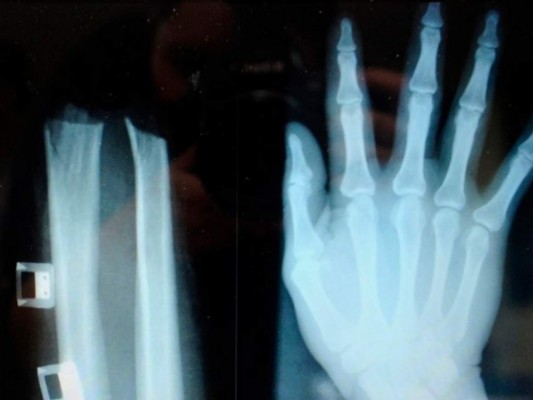

'Junto a un cómplice, se amputó deliberadamente la mano a nivel de la muñeca con una sierra circular con la esperanza de hacer creer que era un accidente', dijo un portavoz de la policía de Liubliana, Valter Zrinski.

La mano pudo ser recosida de urgencia en el hospital universitario de la ciudad.